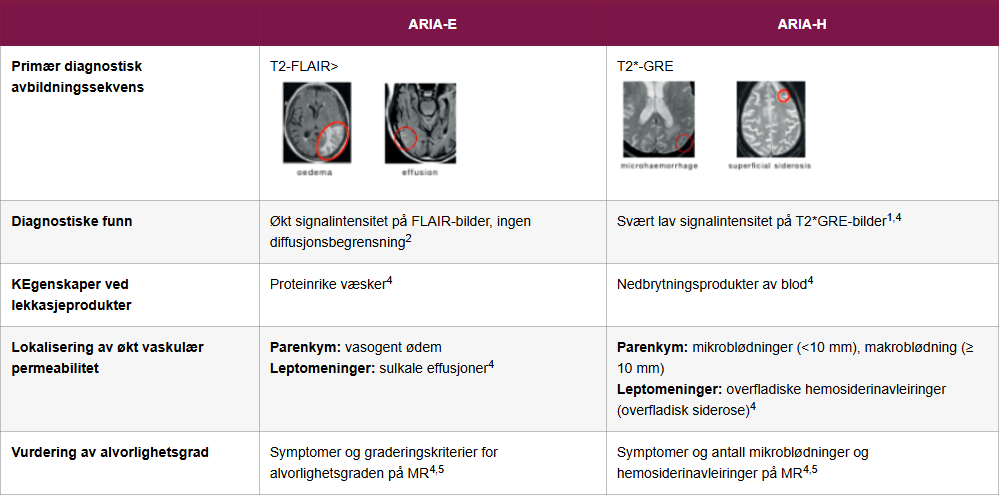

Plasmalekkasje er synlig på FLAIR-sekvenser (Fluid-Attenuated Inversion Recovery) på MR, mens mikroblødninger og siderose oppdages på T2*-vektet MR. Se tabellen nedenfor for en diagnostisk sammenligning mellom ARIA-E og ARIA-H.1,2,4

| ARIA-E | ARIA-H | |

|---|---|---|

| Primær diagnostisk avbildningssekvens | T2-FLAIR> |

T2*-GRE |

| Diagnostiske funn | Økt signalintensitet på FLAIR-bilder, ingen diffusjonsbegrensning2 | Svært lav signalintensitet på T2*GRE-bilder1,4 |

| KEgenskaper ved lekkasjeprodukter | Proteinrike væsker4 | Nedbrytningsprodukter av blod4 |

| Lokalisering av økt vaskulær permeabilitet | Parenkym: vasogent ødem Leptomeninger: sulkale effusjoner4 |

Parenkym: mikroblødninger (<10 mm), makroblødning (≥ 10 mm) Leptomeninger: overfladiske hemosiderinavleiringer (overfladisk siderose)4 |

| Vurdering av alvorlighetsgrad | Symptomer og graderingskriterier for alvorlighetsgraden på MR4,5 | Symptomer og antall mikroblødninger og hemosiderinavleiringer på MR4,5 |